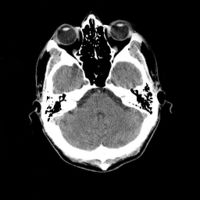

التصوير الطبقي المحوسب CT scan هو أحد وسائل التصوير الطبي تعتمد على الأشعة السينية (أشعة إكس) تستخدم في تكوين صورة ثلاثية الأبعاد لأعضاء الجسم الداخلية. وتتكون عن طريق عدة صور ثنائية الأبعاد تلتقط حول محور ثابت للدوران.

- ويتميز التصوير الطبقي المحوسب بوضوح عالي جدًا للصورة ويُظهِر تفاصيل العظام بشكل متناهي الدقة بعكس تصوير الرنين المغناطيسي الذي يصور الأنسجة الرخوة بدقة عالية.

تعود تسميتها إلى كون هذه الطريقة تعطى صورًا شعاعية على شكل مقاطع للجسم، يجري التصوير الطبقي المحوسب بواسطة جهاز خاص، يسمى جهاز التصوير الطبقي المحوسب أو الماسحة المقطعية المحوسبة، تتميز هذه الطريقة بدقتها، تعطي صورًا واضحة، ويمكن أن تعطي صورًا لأماكن قد تكون من الصعب تصويرها بالتصوير الشعاعي التقليدي، كذلك يمكن عملها بشكل سريع ودقيق.